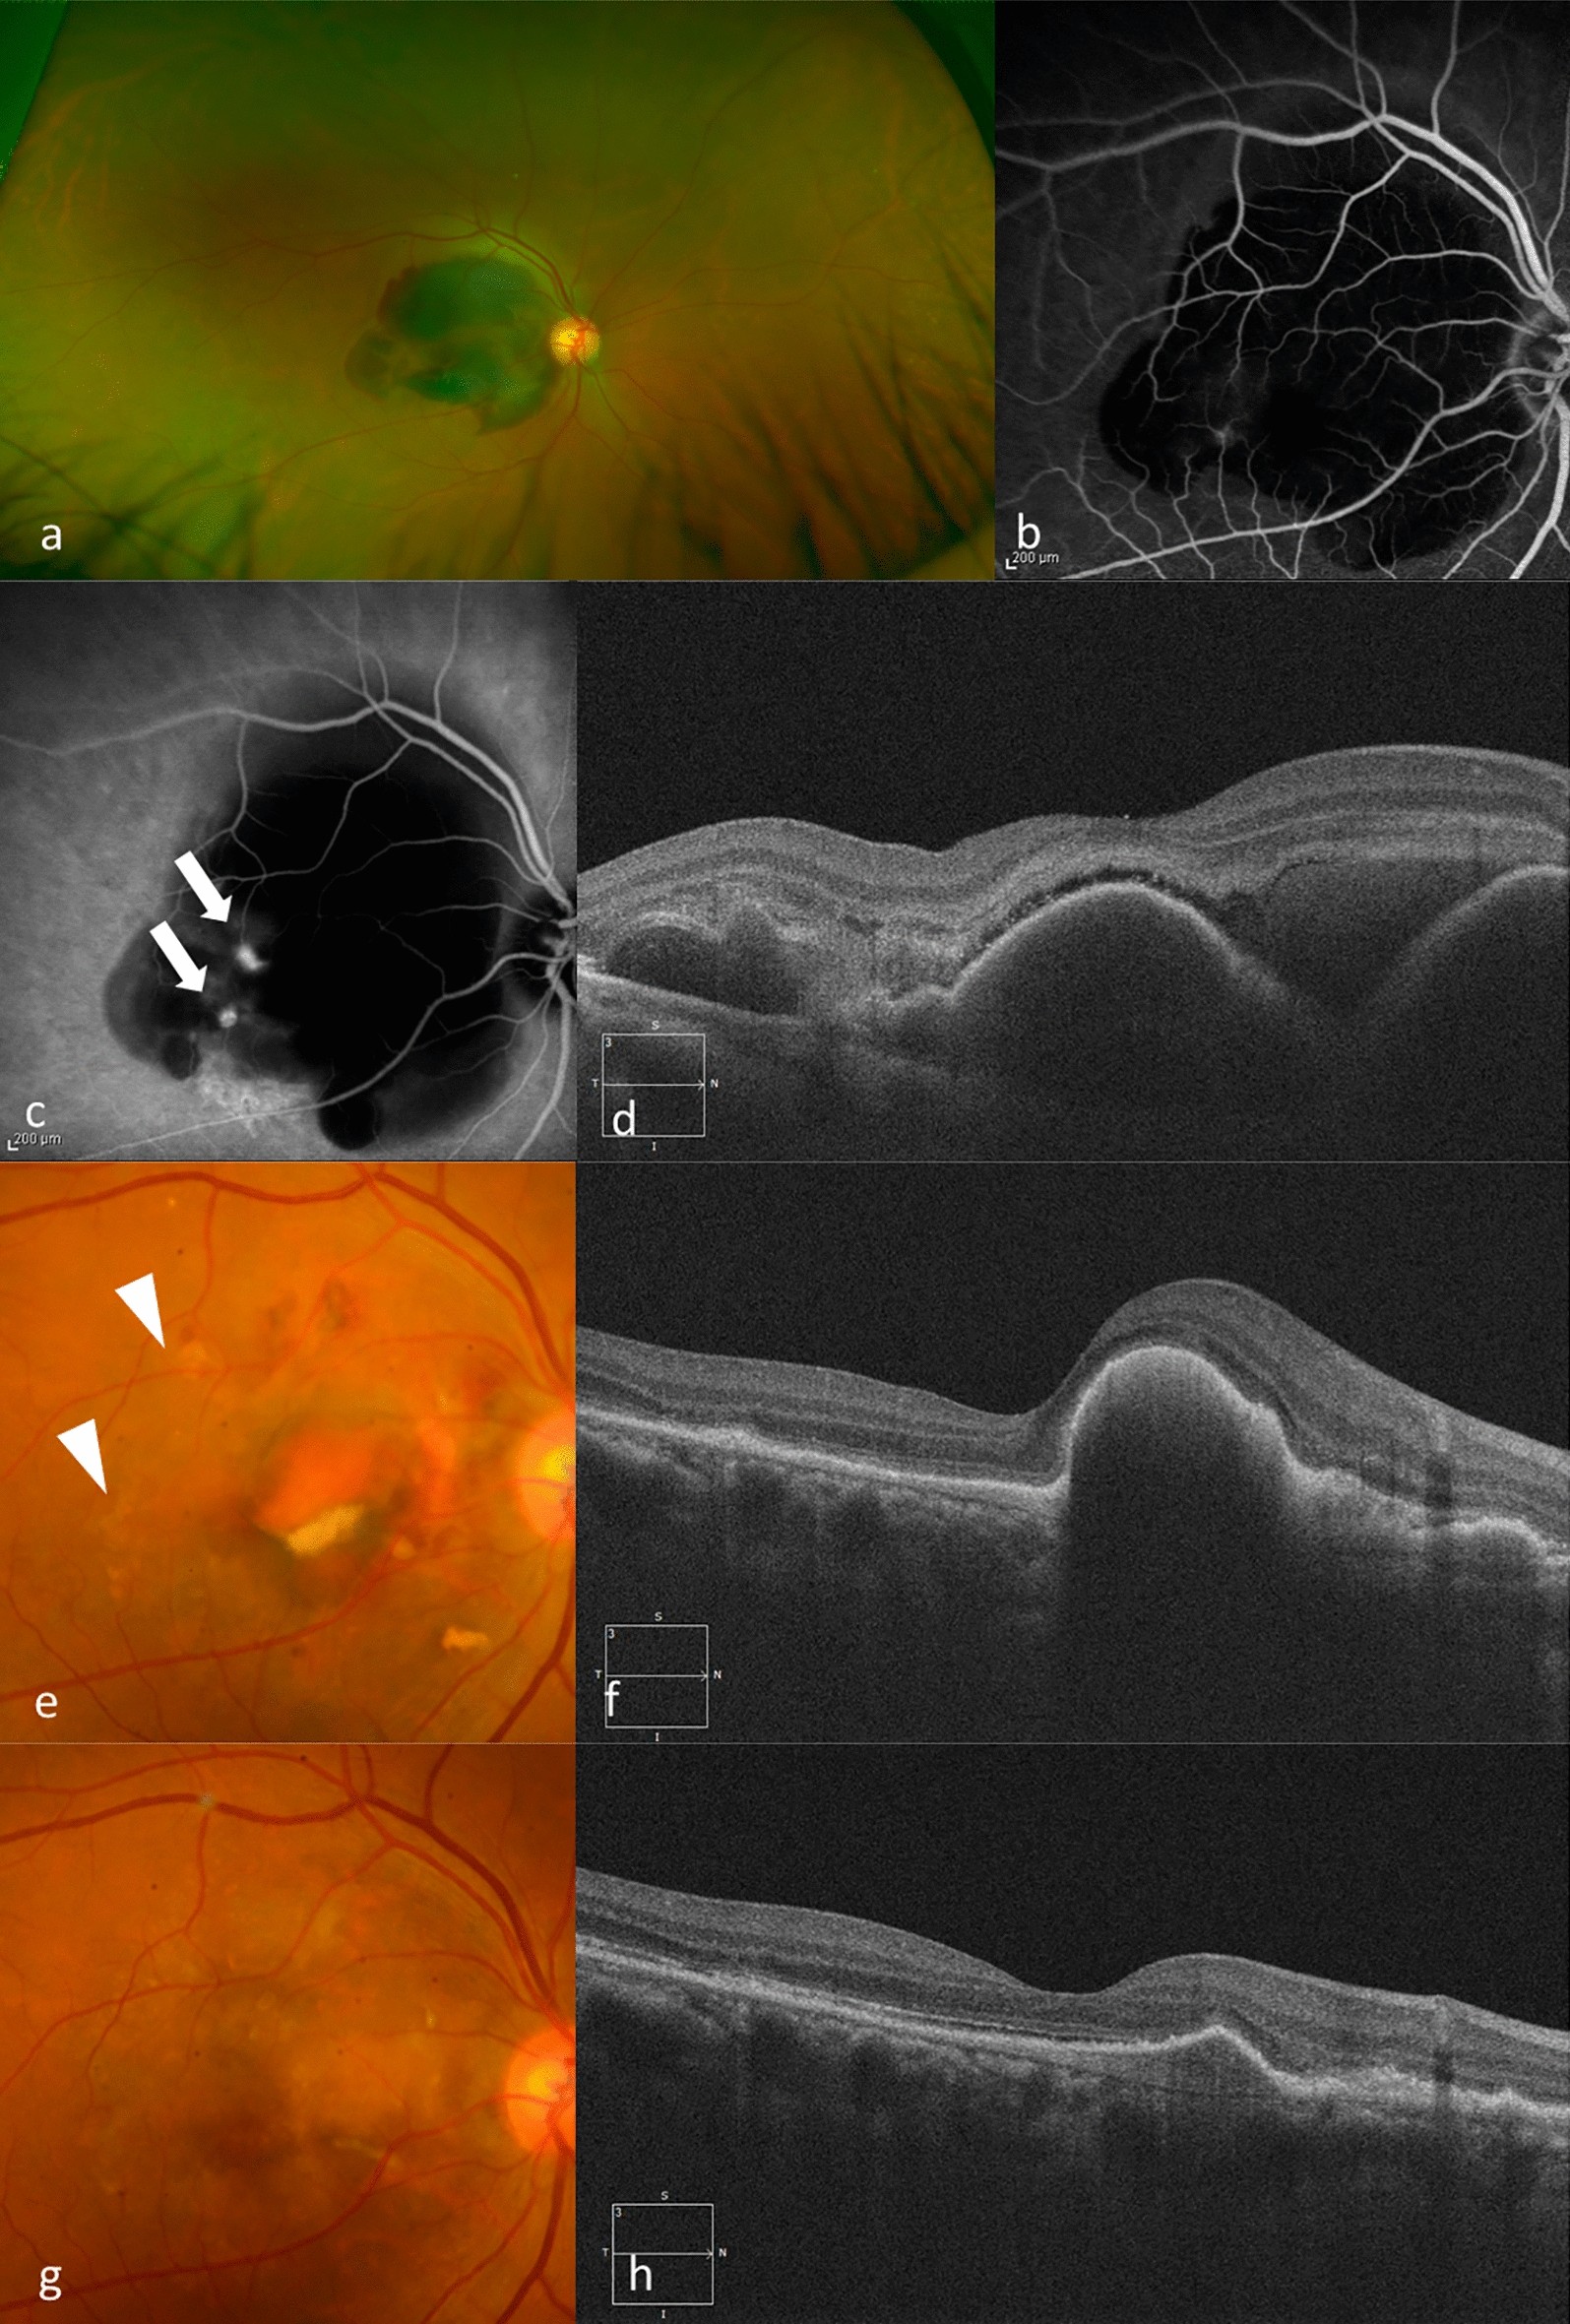

Figure 3

(a) A 60-years-old woman presented with sudden visual loss in her right eye (BCVA 20/30). Funduscopic examination in that eye shows a SMH in the macula. (b) Fluorescein angiography shows blockage due to the hemorrhage. (c) Indocyanine green angiography shows a polypoidal lesion and an abnormal vascular network (arrows). (d) A baseline OCT image shows a SMH and hemorrhagic PED. She was diagnosed PCV and received IVA treatment monthly during the loading phase. (e) Fundus photography at 3 months shows that the SMH resolved. Hyperpigmented spots are noted (arrowheads). (f) OCT at 3 months still shows a hemorrhagic PED. (g) Fundus photography at 1 year shows no SMH. Her BCVA improved to 20/20. (h) SD-OCT at 1 year shows improvement of the hemorrhagic PED.